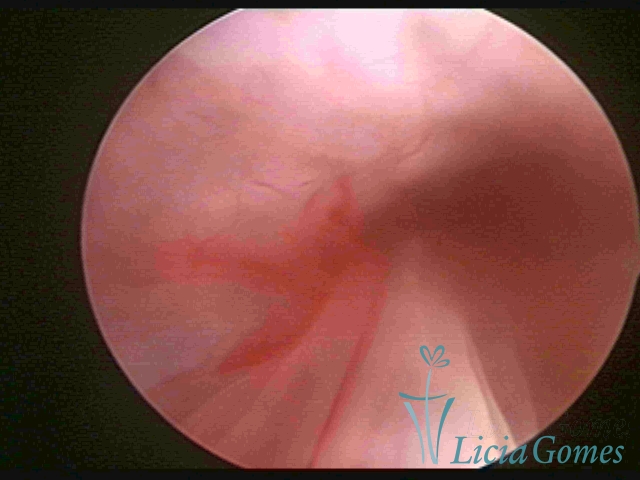

PÓLIPOS ENDOCERVICAIS

São tumores benignos, resultantes da proliferação focal reativa aos processos inflamatórios ou à situações de hiperestrogenismo, e podem ter sésseis (com a base de implantação larga) ou pediculados do epitélio.